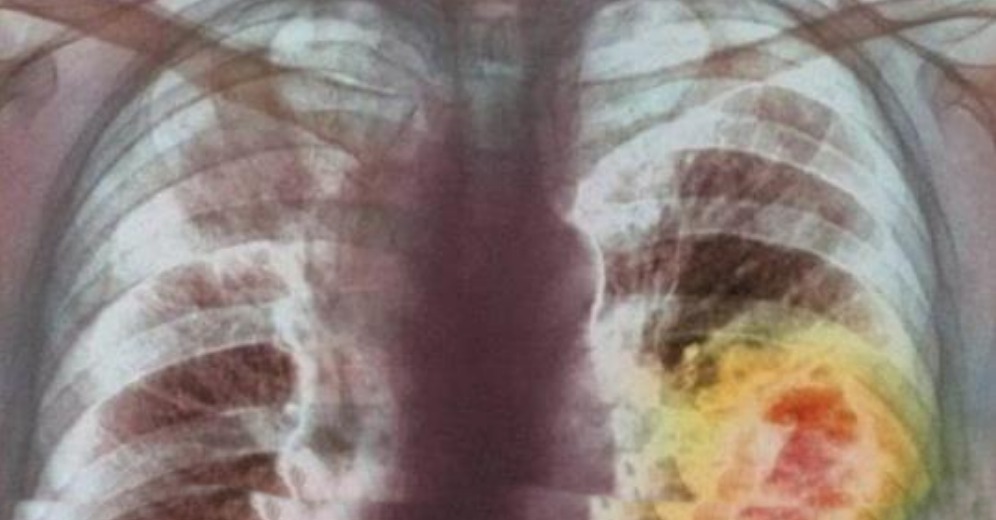

Евгений взял пациентку, которую называли безнадежным случаем. 17-летнюю Ирину отказывались лечить десятки врачей, но Евгений бросил себе настоящий вызов, проведя 18-часовую операцию, удаляя 42 метастазы из легкого пациентки!

Но даже после удаления метастаз, было понятно, что в легком осталось множество микроскопических отростков, которые рано или поздно проросли бы. Тогда Евгений принял решение использовать метод изолированной химиоперфузии.

Этот метод позволил обработать легкое концентрированным составом химических лекарств. Для этого врачи отключили на некоторое время легкое от общего кровотока.